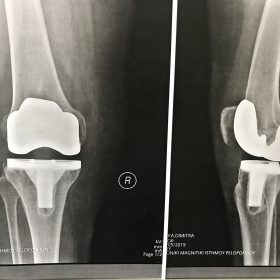

Σε αυτό το σημείο η Αρθροπλαστική Γονάτου αποτελεί μονόδρομο.